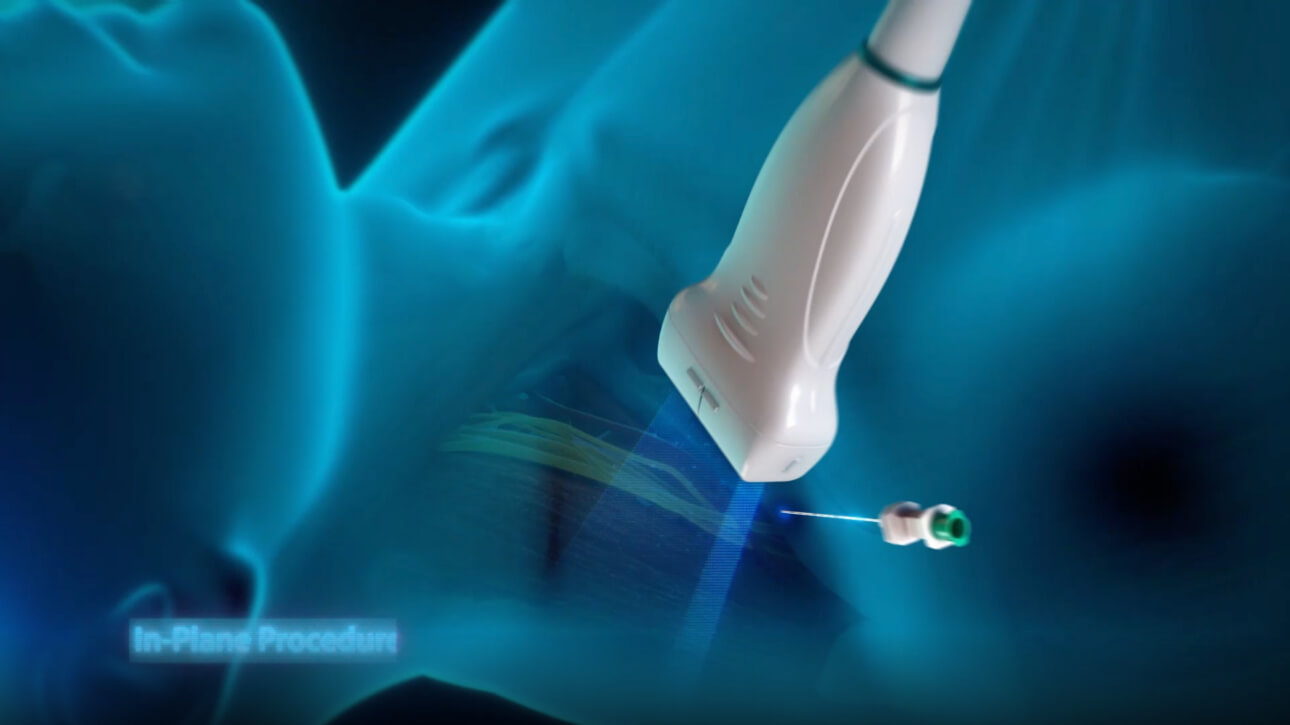

With its superior image quality, simple touchscreen operation and class-leading intelligent tools, the Mindray TE7 ACE is designed to simplify and speed-up ultrasound examinations.

Its versatility makes it suitable for demanding point-of-care environments including Critical Care, Emergency and Anaesthetics.